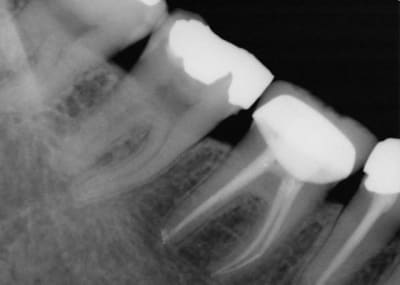

J'avais couronné... mais démontable, pas d'IC...

3 ans après (oui, on devait surveiller tous les 3 mois ;-)

De l'intérêt de pouvoir facilement démonter.

(radio 3 mois après)

Voilà la fin.

La première radio du post était de 2006, c'était une bio classique, pas de nécrose, grosse carie juxta pulpaire.

Les deux dernières sont de 2011 et 2015.

J'ai posté ça car j'ai vu la patiente hier.

Tout ça pour dire que les voies de l'endo sont parfois impénétrables...